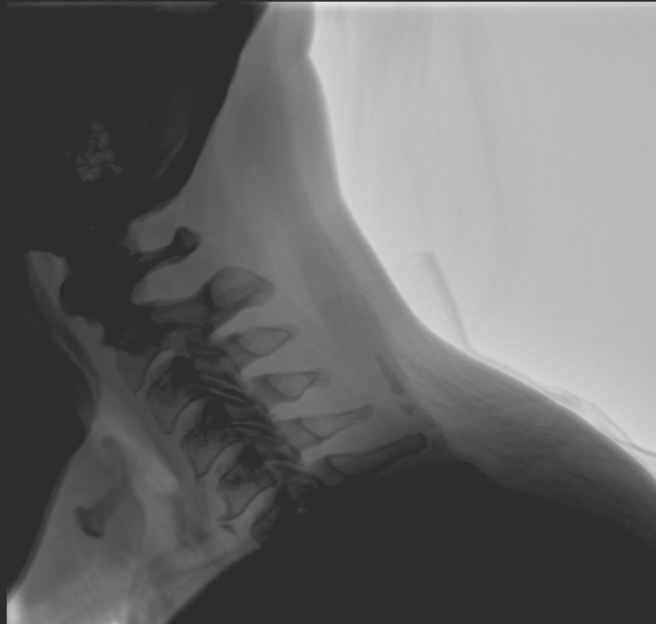

平板尺寸升級 呈現(xiàn)更多解剖細節(jié)

采用30CM×30CM大尺寸動態(tài)平板探測器,成像面積較傳統(tǒng)平板探測器大幅提升。

圖像清晰細膩

高清像素,低信噪比,細小的組織結構也可以清晰顯示。

Clinical picture

臨床圖片